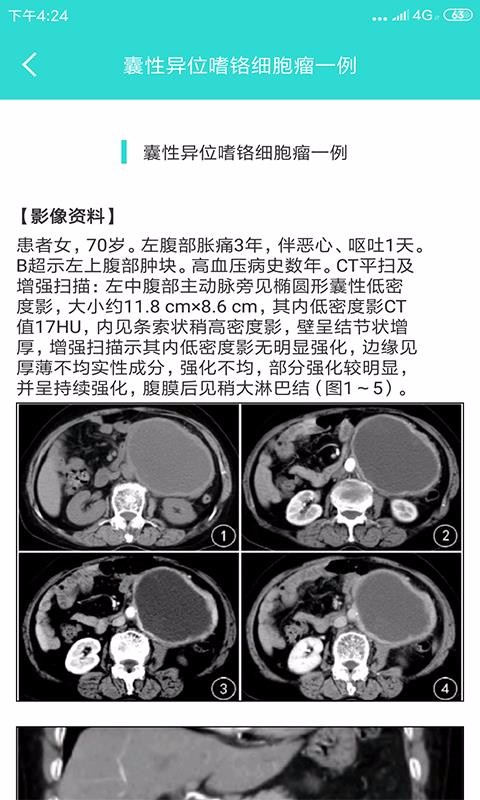

影像图鉴app是为大家收集了很丰富的影像案例,帮助用户解决读片的困惑;非常清晰的影像图片,还有相关的介绍资料,让您在学习的时候更方便,通过观看到的影像图片自主读片,从影像当中读取患者的身体情况;同时,在学习知识的时候可根据关键字信息搜索相关内容,帮助查找影像学习资料,开始高效学习;不仅如此,系统还为医生提供了医学解刨方面的相关学习资料,以人体结构的不同,分类学习解刨知识,轻松掌握人体每一个部位的特点,轻松提升医生用户的专业能力,欢迎有需要的朋友下载软件使用。

详细分析,每一张影像图片都有相关的分析内容,致力于帮助用户看懂不同医学影像;

提供的影像图片非常的清晰,支持用户将提供的图片放大处理;

可以根据查看到的影像图片自主分析,学习独立分析影像图片;